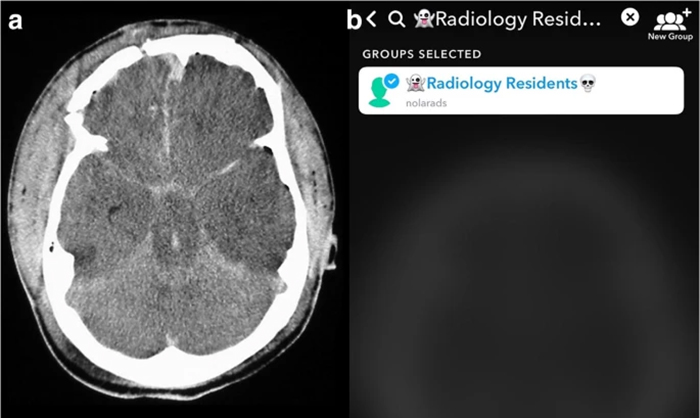

The team compared image analysis and interpretation by radiology residents using Snapchat on smartphones with conventional analysis on a single screen in the resident conference room.

“All cases used were diagnoses considered to require emergent, non-routine communication on the order of minutes to the ordering health care provider,” notes Bradley Spieler, MD, Vice Chairman of Research in the Department of Radiology at LSU Health New Orleans School of Medicine. “As such, these types of diagnoses demand prompt imaging recognition as they are considered critical findings which could result in death or significant illness if not acted upon expeditiously.”The team chose Snapchat, a social media app allowing communication via video and digital images with text messaging functionality, not only because of its popularity with young adults, but most importantly because unlike other image based social media platforms, Snapchat allows for the timing of image visibility by users. The ability to specify the length of time an image is visible to a user (or trainee in this scenario) in rendering an image-based diagnosis creates an intriguing potential for innovation in radiologic curricula, particularly as it relates to assigning a metric to diagnostic performance.

“All residents performed better on Snapchat each week,” says Dr. Spieler, who is also an Associate Professor of Radiology, Internal Medicine, Urology, & Cell Biology and Anatomy at LSU Health New Orleans. “Their accuracy rate was higher using Snapchat than a traditional classroom screen.”